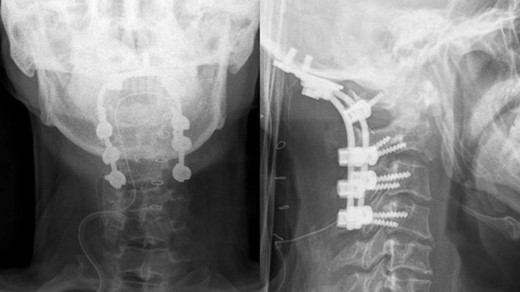

Following the surgery, the patient remained an inpatient for 5 days and was subsequently discharged from our ward. The patient reported a reduction in tingling sensations in both hands and feet. A postoperative X-ray confirmed the successful occipitocervical fusion with a well-maintained screw trajectory (Fig. 4).

Postoperative x-ray showed proper occipitocervical stabilization.